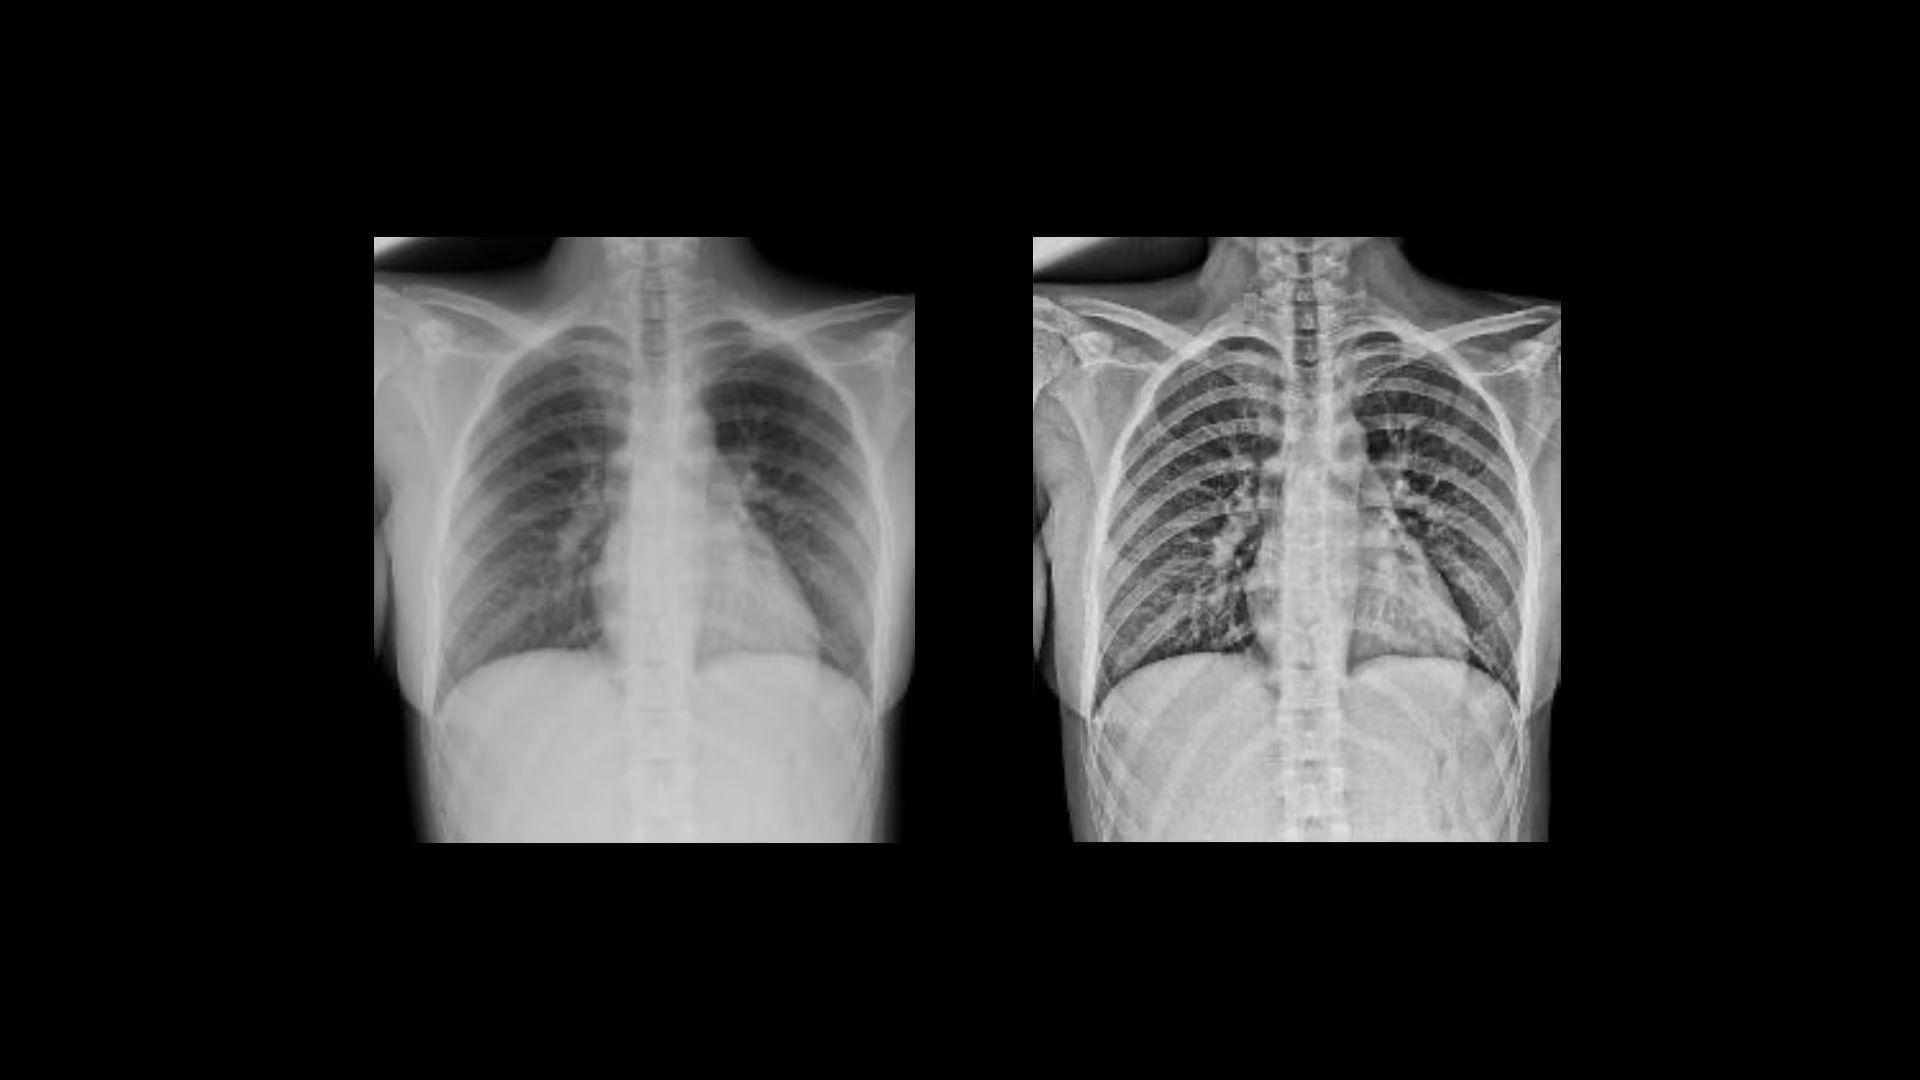

Clarity

Local Contrast Enhancement (LCE) increases local contrast in both pediatric and adult chest X-ray images for better visualization of the lungs, heart, and spine regions. It is also available for ankle joint (AP), foot (AP), and patella (tangential)*, and has three levels of enhancement (low, medium and high).